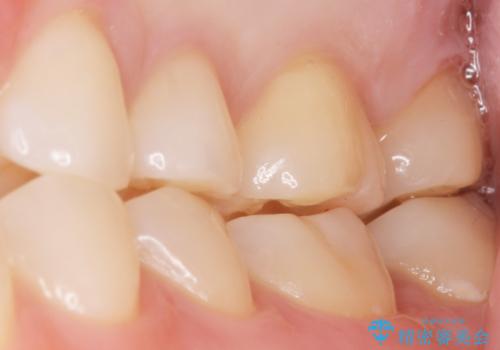

審美的な仕上がりと自然な咬み心地にご満足頂けました。

治療終了後も定期的にクリーニングとホワイトニングで通院して下さっています。

インレーの種類:セラミックインレー(e-max press)